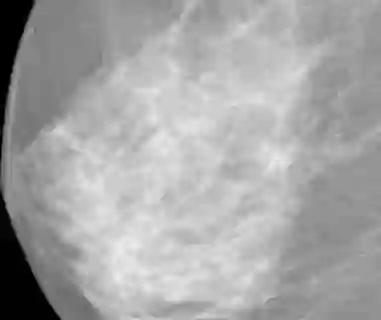

The deep learning technique has been shown to be effective in addressing several image analysis tasks within the computer-aided diagnosis scheme for mammography. The training of an efficacious deep learning model requires large amounts of data with sufficient diversity in terms of image style and quality. In particular, the diversity of image styles may be primarily attributed to the vendor factor. However, the collection of mammograms from large and diverse vendors is very expensive and sometimes impractical. Motivatedly, a novel contrastive learning method is developed to equip the deep learning models with better generalization capability. Specifically, the multi-style and multi-view unsupervised self-learning scheme is carried out to seek robust feature embedding against various vendor styles as a pre-trained model. Afterward, the pre-trained network is further fine-tuned to the downstream tasks, e.g., mass detection, matching, BI-RADS rating, and breast density classification. The proposed method has been extensively and rigorously evaluated with mammograms from various vendor-style domains and several public datasets. The experimental results suggest that the proposed domain generalization method can effectively improve the performance of four mammographic image tasks on data from either seen or unseen domains and outperform many state-of-the-art (SOTA) generalization methods.